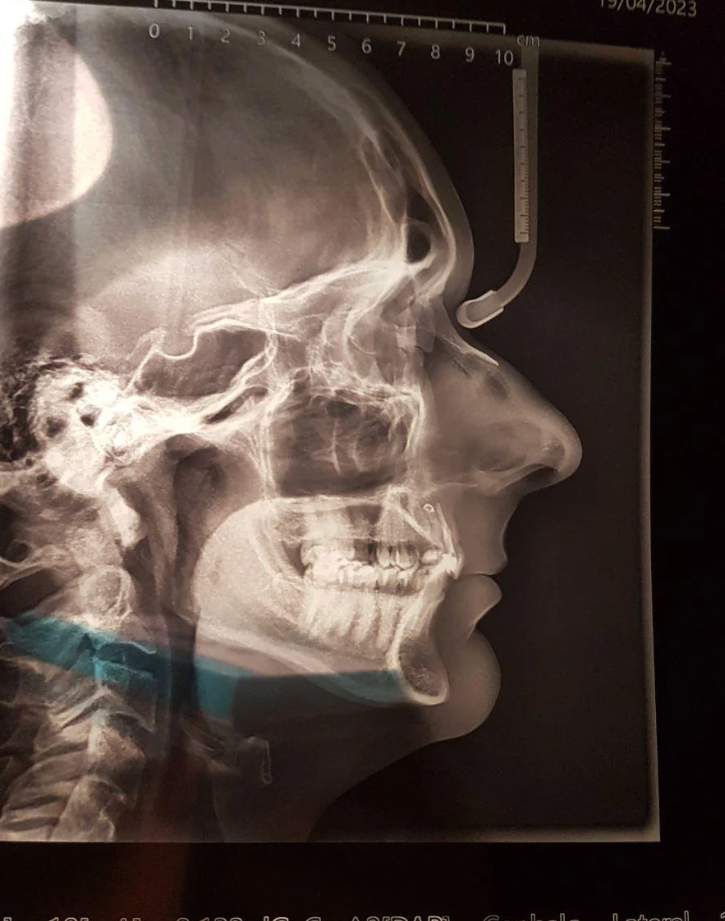

Images